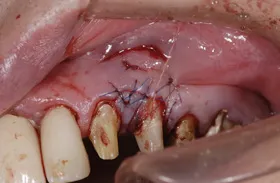

治療のポイント

- 右上奥の骨 → 骨をつくりました

- 前歯を支える歯茎 → 歯茎の幅をつくりました

- 左下奥の歯肉 → 歯肉を移植しました

骨が深く欠損していた箇所は骨を作り、歯茎が薄くなっていた箇所は増大させました。

また左下奥インプラントを支える歯茎が柔らかく、歯磨きが困難な為、歯肉を移植し丈夫な歯茎にしました。

| 主訴 | 上顎の前歯が割れて噛むことができない |

|---|---|

| 治療方法 | かみ合わせが低くなり、下の歯が上の歯に対して、突き上げていたのでかみ合わせの高さを修正し突き上げをなくした |

| 治療期間 | 約2年 |

| 通院回数等 | 40回 |

| 費用 | 5,500,000円(税込) |

| リスク・副作用 | 外科的に骨を作る為、治療後に腫れることがある |